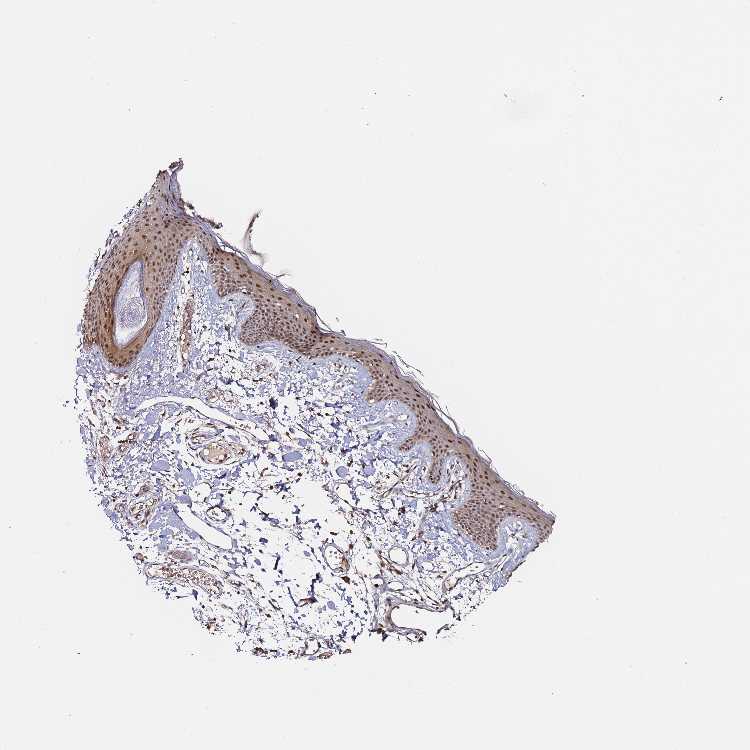

SKIN 1 - Antibody stainingi

Antibody staining in the annotated cell types in the current human tissue is reported as not detected, low, medium, or high, based on conventional immunohistochemistry profiling in selected tissues. This score is based on the combination of the staining intensity and fraction of stained cells.

Each image is clickable and will lead to virtual microscopy that enables deeper exploration of all samples and also displays staining intensity scores, fraction scores and subcellular localization as well as patient and tissue information for each sample.

Antibody HPA045780

Langerhans Medium

Fibroblasts Medium

Keratinocytes Medium

Melanocytes Medium